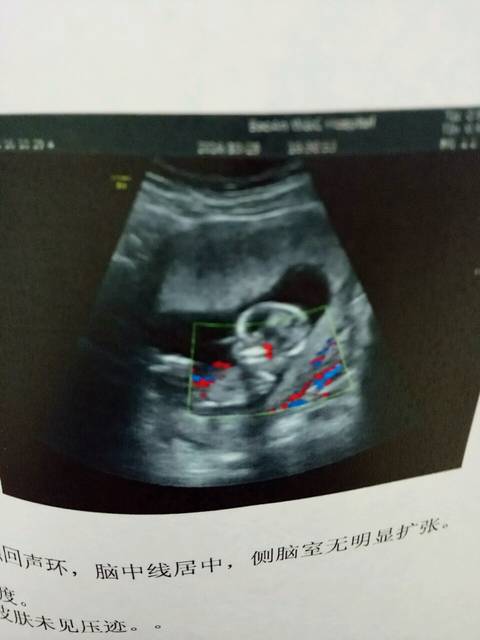

NT顺利,求科普B超照里的红线蓝线是什么意思